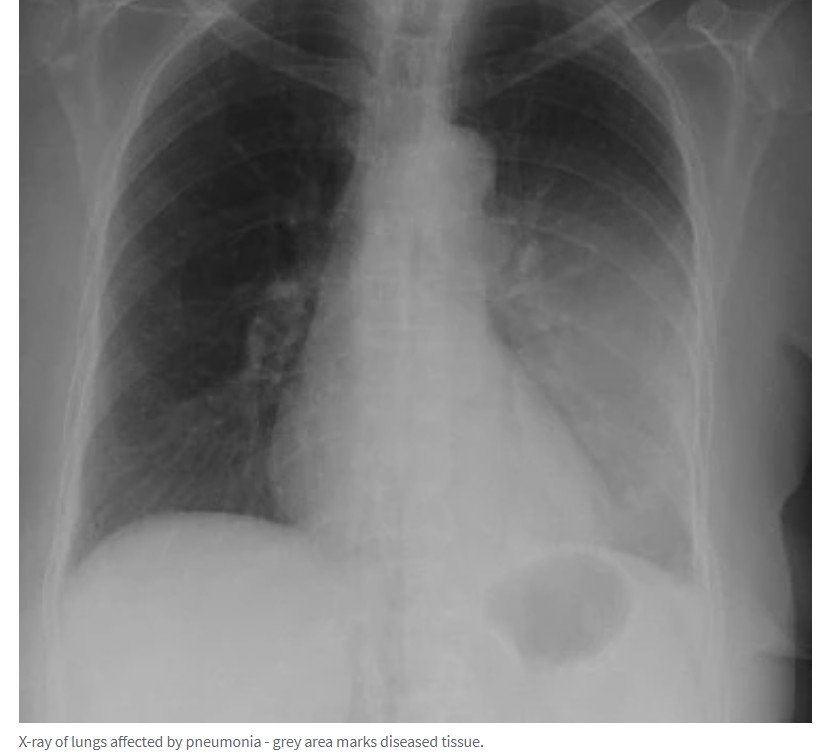

据悉,昆州近两万名儿童患上了发病率急剧上升的肺炎。 卫生专家透露,用于治疗这种严重疾病的抗生素出现了长达三个月的短缺。 "之所以称之为行走性肺炎,是因为这种疾病通常不会导致患者生病住院,但也 ...